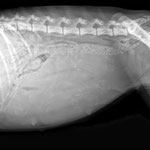

Hündinnen tragen normalerweise 63 Tage. Da man aber (ohne aufwändige medizinische Tests) den genauen Zeitpunkt des Eisprungs nur nach dem Datum der Deckungsbereitschaft der Hündin abschätzen kann, bleibt auch der voraussichtliche Wurftermin nur eine Schätzung. Erst ab dem 25. Trächtigkeitstag kann man mittels Ultraschall feststellen, ob die Hündin überhaupt trägt. Ihr äusserlich ansehen kann man das sogar erst ab ungefähr dem 40. Tag. Es könnte ja aber auch immer noch eine Scheinträchtigkeit sein. Gewissheit gibt ein Röntgen, das ab dem 45. Tag gefahrlos gemacht werden kann.